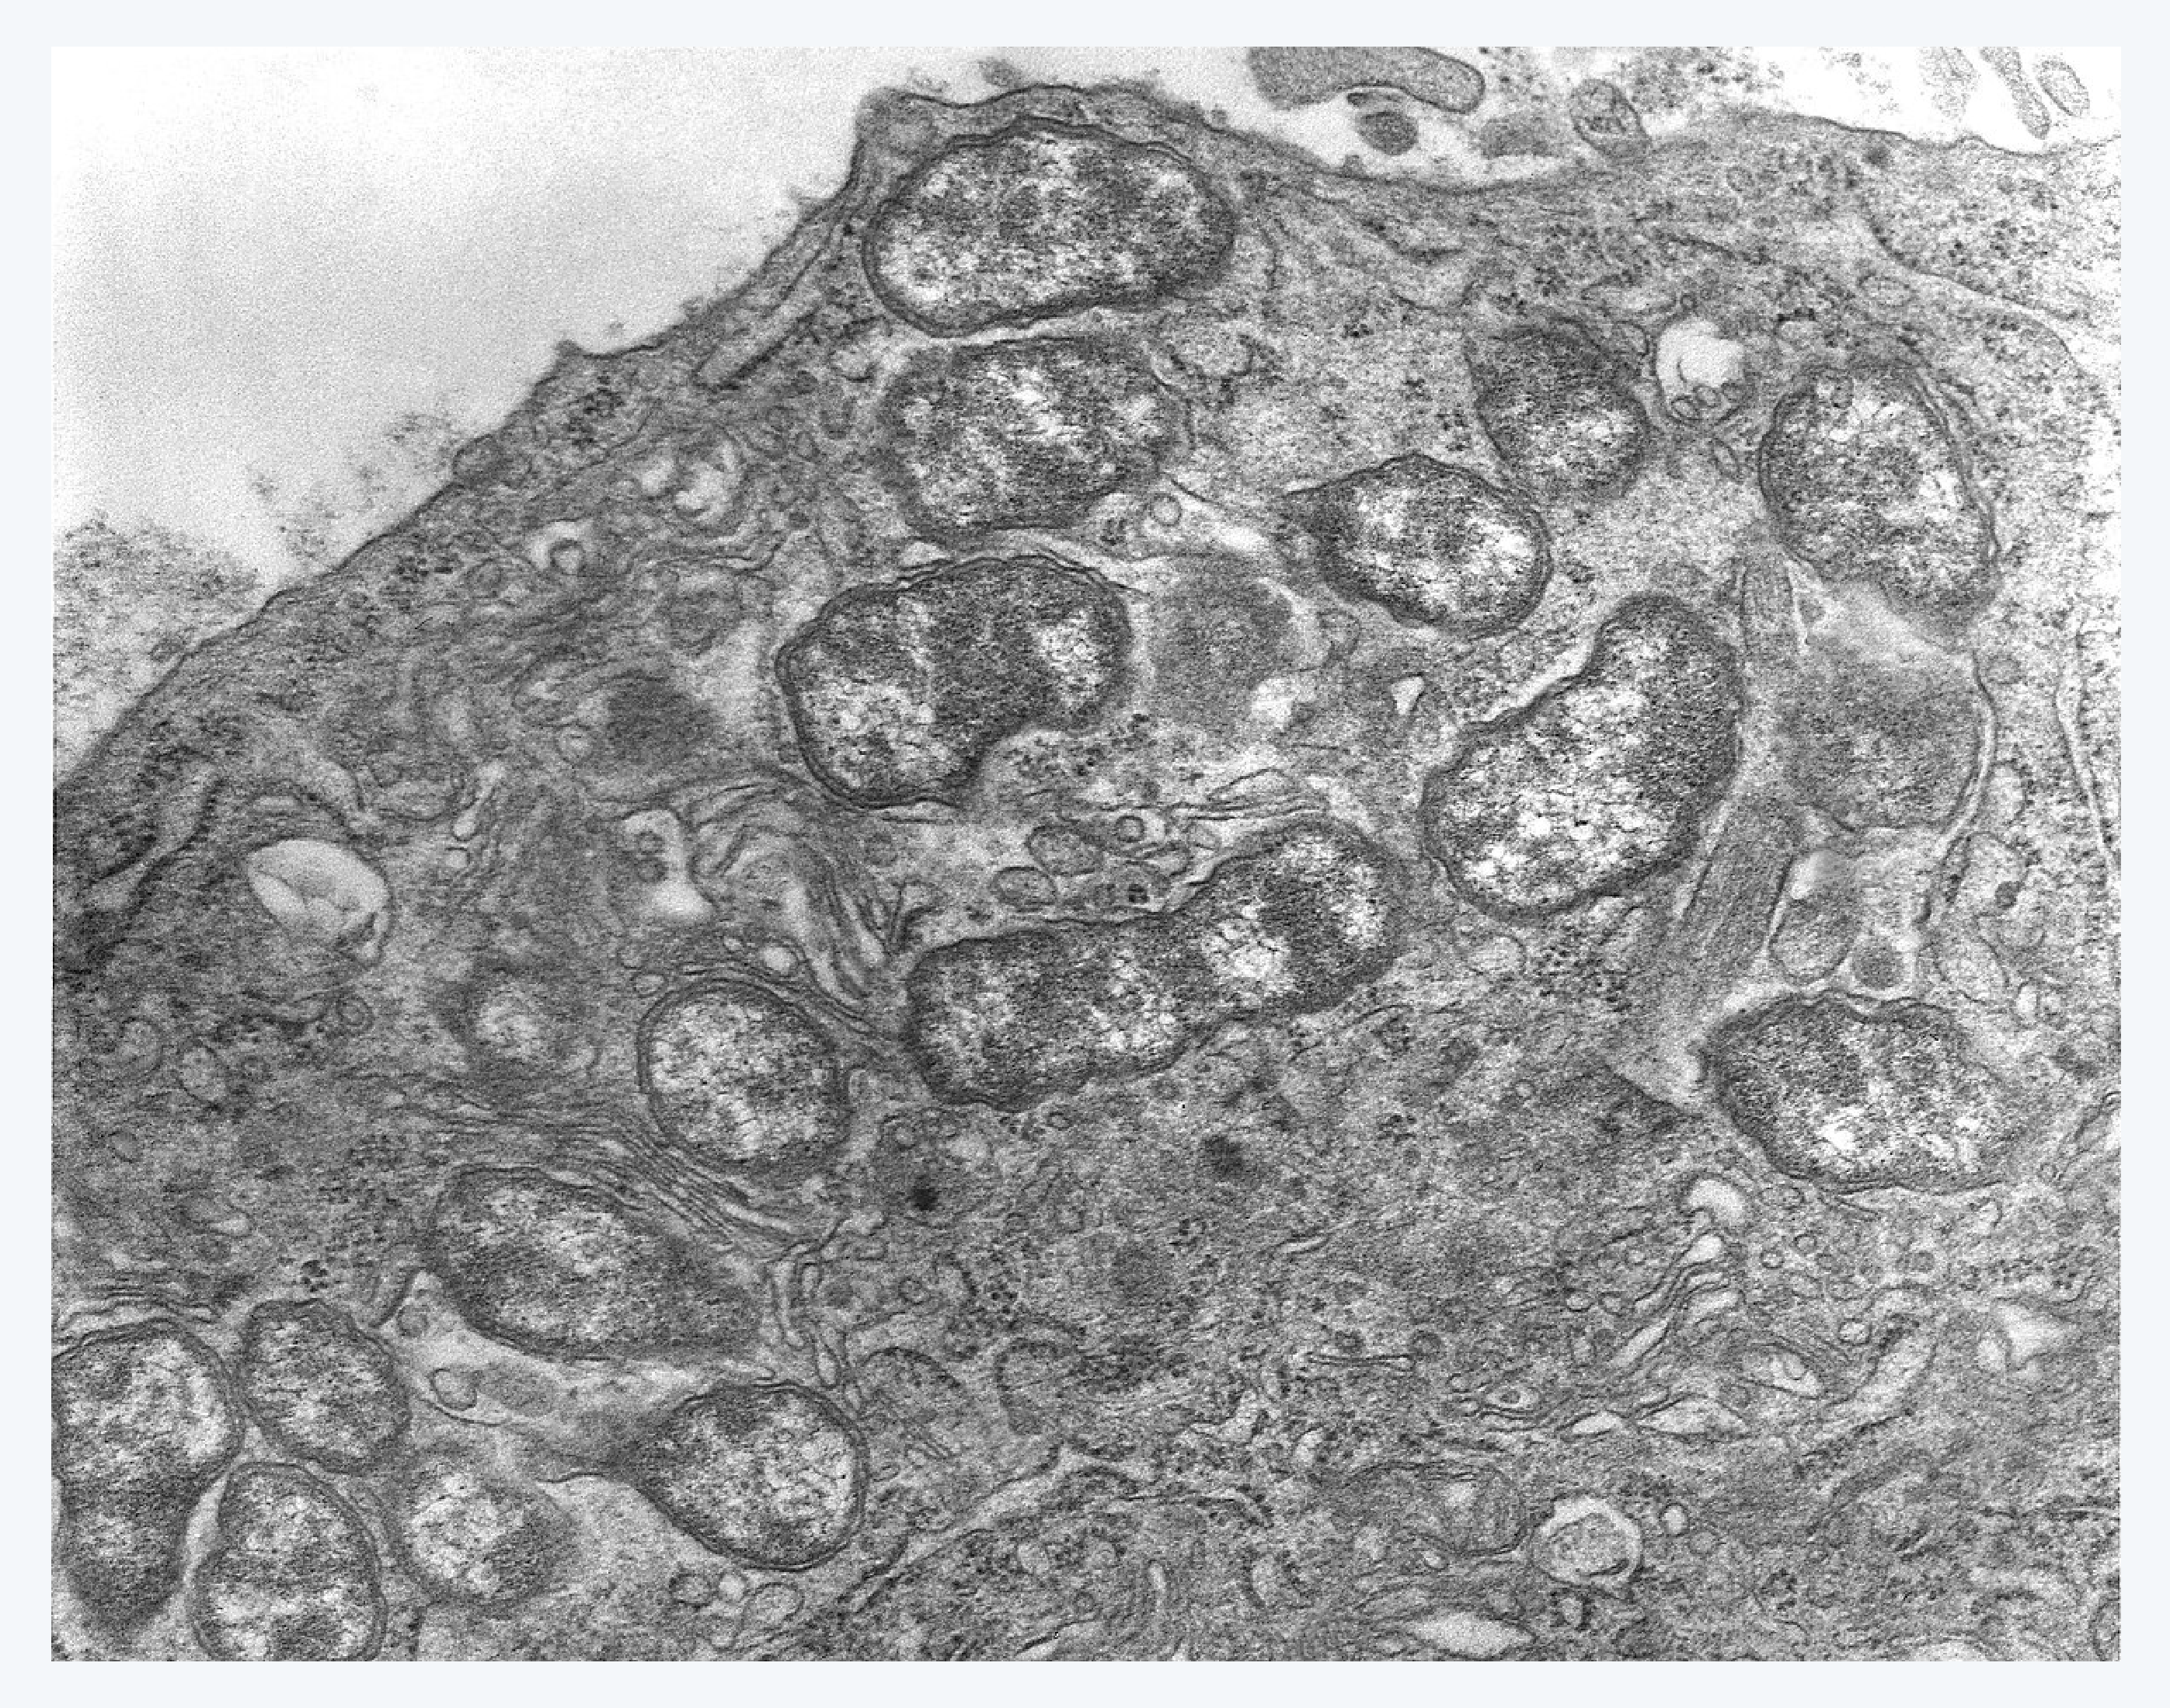

쯔쯔가무시(Orientia tsutsugamushi) : 세포 내 기생세균으로서 김자(Giemsa) 염색을 하면, 그람음성 간구균(Coccobacillus) 모양으로 보통 직경은 0.5~0.7㎛, 길이는 1.2~2.5㎛로 측정됩니다.

쯔쯔가무시 (출처: 위키피디아)